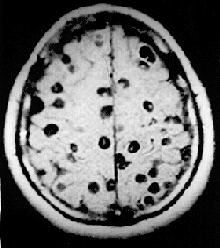

| Magnetic resonance image (MRI) in a person with neurocysticercosis showing many cysts within the brain. | |